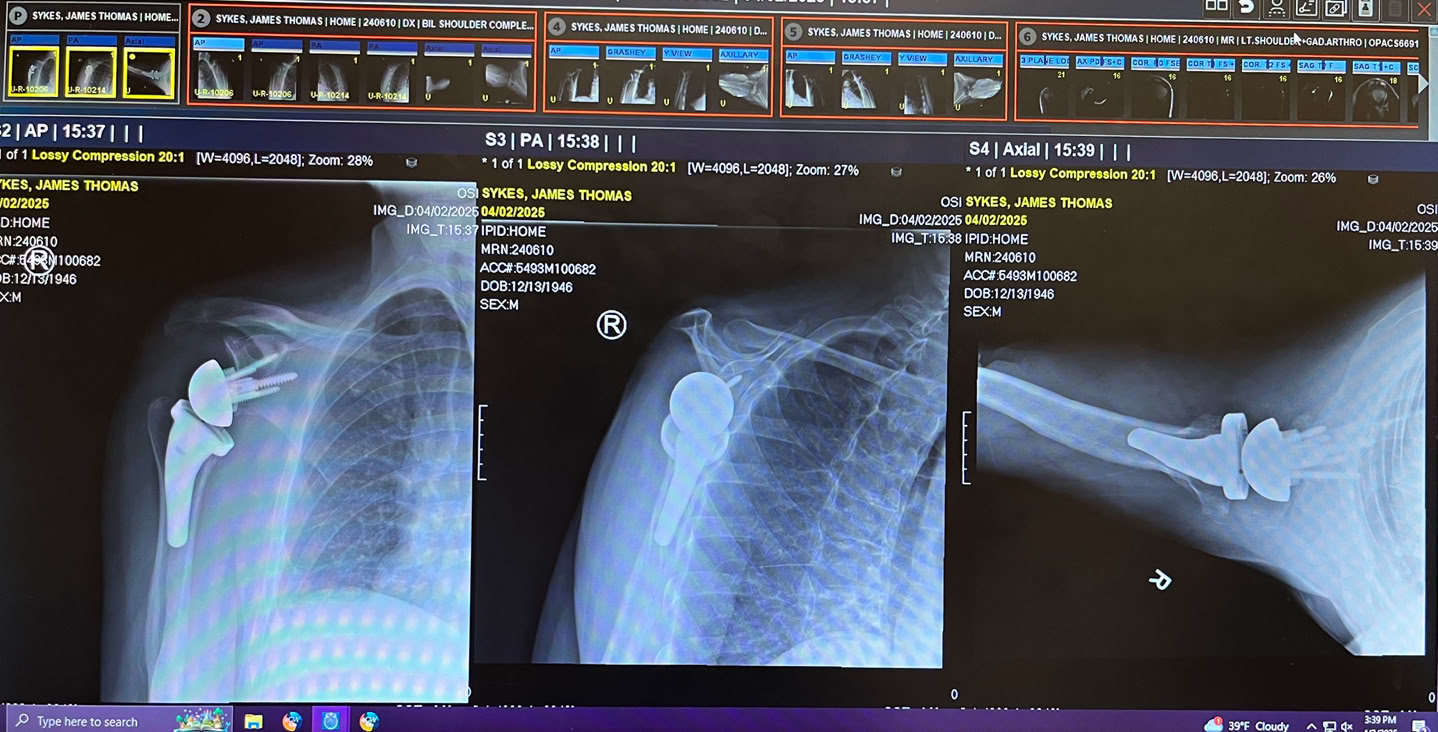

January found us heading to northern Minnesota to catch up with winter birding, something we’d not done for years.  February was Tom’s reverse shoulder replacement surgery (followed by months of physical therapy). April it was Carol’s turn - a new hip. And more PT. As we were once more living in Wisconsin, there was not need for an annual return visit. Instead we availed ourselves of farmers markets, supper clubs and seeing more of family. However, August required a trip west to Wyoming to attend granddaughter Cali’s outdoor wedding to her fiancé Daniel. September held two reunions. One for Carol’s family and the second Tom’s 60th high reunion. By the time November rolled around it was time for our bird tour to Northwest Argentina. Alas, owing to some unseen physical issues, Carol’s mobility prevented her from going on the tour. Shortly after Tom’s return from Argentina, it was time for his second reverse shoulder replacement surgery. The remainder of the year will be overshadowed by more physical therapy as we work our way through the holidays.